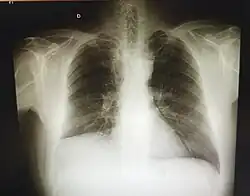

![]() Pulmón extirpado mediante una neumonectomía por cáncer de pulmón (la lesión blanquecina cerca de los bronquios). | ||

La neumonectomía consiste en la extirpación quirúrgica total o parcial de uno o ambos pulmones. La neumonectomía parcial, también conocida como lobectomía pulmonar, consiste en la extirpación de una sección pulmonar (lóbulo). La operación se practica, casi siempre, como tratamiento del cáncer de pulmón, aunque puede ser necesaria una lobectomía en algunos casos de tuberculosis, bronquiectasias o absceso pulmonar.